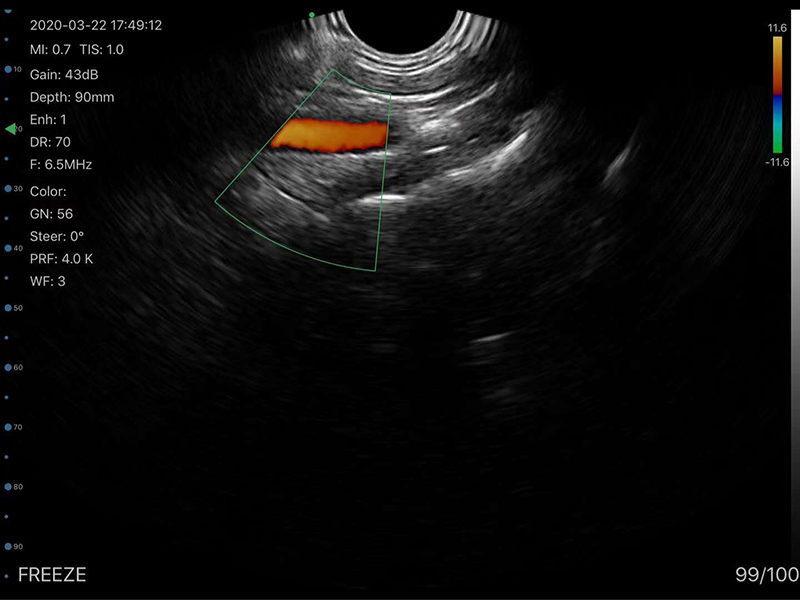

• 显示模式:B、B/M、Color、PW、PDI

• 穿刺辅助功能:平面内穿刺引导线功能,平面外穿刺引导与血管自动测量功能,针尖显影增强功能